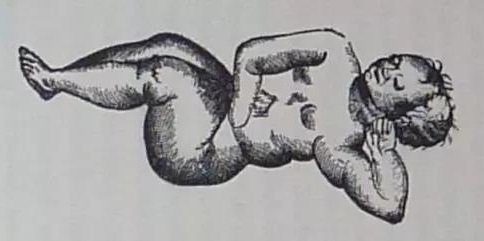

外科医生纪录的桑斯胎儿的形象

这里面竟是一个蜷缩着的女胎,连头发纹理、牙齿以及未闭合的囟门都清晰可见。

她的头部略微朝左倾斜,并由左臂支撑。

其右臂则向肚脐位置延伸,半截手臂末入腹中。